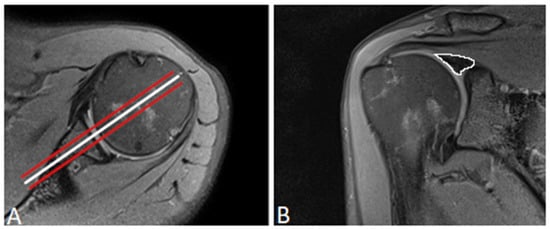

2.5. Placement of Regions of Interest